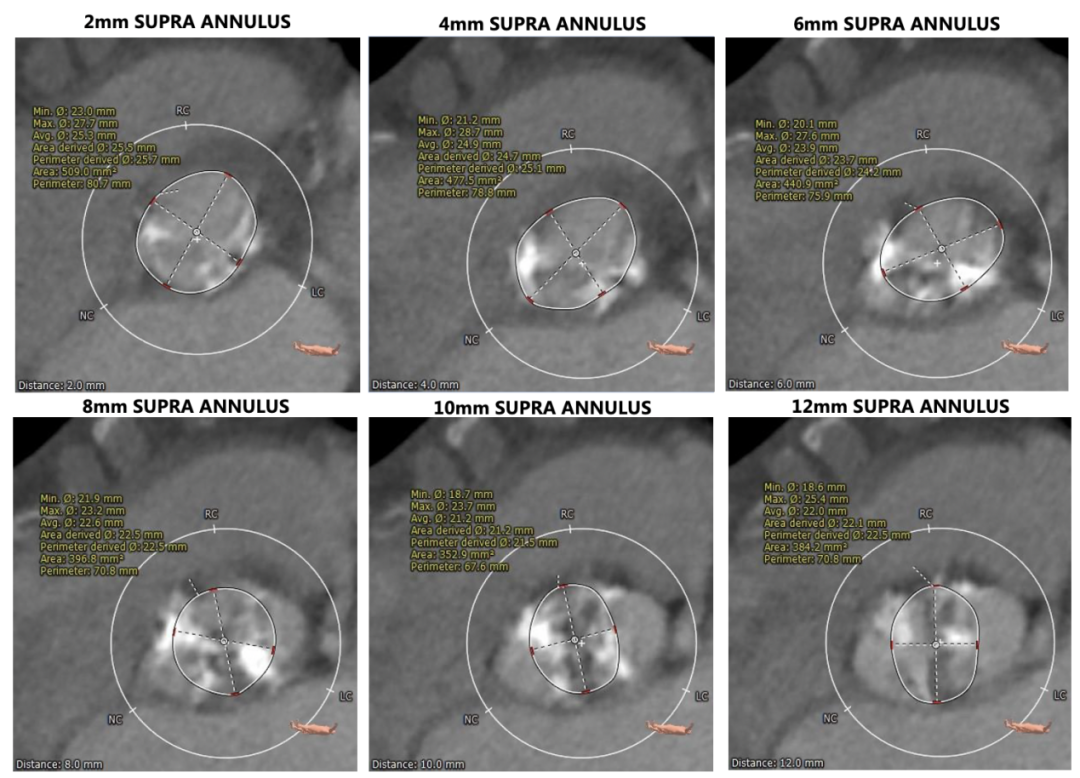

主动脉根部测量

瓣环上结构评估

Type0型二叶式主动脉瓣,瓣叶中度钙化并纤维增厚,钙化似云雾状分布于两侧瓣叶。

左冠开口高度稍低,左冠瓣长度偏长。

非横位心,主动脉弓角度与宽度合适。入路血管局部钙化,双侧血管内径良好,整体入路血管条件较好。